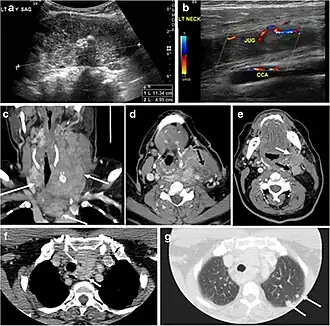

Fig. 9. A 58-year-old male patient with persistence PTC at thyroid bed with hypervascular nodal metastasis. a–c Transverse greyscale and colour Doppler neck ultrasound demonstrate hypoehoic soft tissue in the left thyroid bed (white arrow in a). There are a heterogeneous enlarged lymph nodes at level 2 and 3 with markedly increased vascularity (white arrow in b and c). d–f Enhanced axial CT images of the neck demonstrate a 2.7 × 1.4 cm hypodense soft tissue lesion anterior to the left carotid sheath (white arrow). There are left-sided enhancing abnormal and enlarged lymph nodes at cervical level 2 and 3 (black arrows).[1]